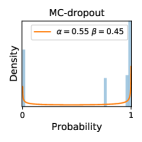

5.1 Distribution of Uncertainty Scores

Distribution of Uncertainty Scores Across Different Severity Levels As explained in Section 3, each uncertainty metric essentially defines an order/ranking among the data points. We conducted an analysis to better understand what data will be assigned high uncertainty under a particular uncertainty metric . Picking out the highest ranked data points (), we calculated the ratio of data points from each SL. Figure 4 summarizes the results as box plots for the Kaggle-DR and the Messidor-2 datasets; additional detailed statistics can be found in Table S.1 in the supplementary materials. From the plot and table, SL1 & SL2 examples account for a higher proportion among the top-ranked uncertain examples across the three ensemble methods. This finding matches our intuition that incipient disease examples (SL1 & SL2) are more likely to be considered uncertain by ensemble methods due to their ambiguity.

Comparing the three ensemble methods in Figure 4, the stacking ensemble method has the highest ratios of SL1 & SL2 data among the high-uncertainty examples it identified under both mean and var. TTA showed slightly better performance than MC-dropout but still falls behind the stacking ensemble method. Considering the fact that SL0 examples accounted for the majority of the dataset, the stacking ensemble method was much more precise (specific) in selecting truly ambiguous data points that were difficult to classify. From Figure 3, we can also see that the stacking ensemble method greatly outperformed the other two methods in finding false negatives under both mean and var uncertainty metrics.

In contrast, the MC-dropout method showed the worst overall performance among the three, as it can be seen from the high ratios of SL0 examples among the uncertain negatives in Figure 4. The histograms in Figure 2 provides another perspective to look into the phenomenon, where a decent proportion of MC-dropout model’s predictions on SL0 inputs entailed low confidence (far from 0 or 1), which from another angle explained why MC-dropout was less specific in terms of lower FNP; many no-DR inputs (i.e. SL0) were erroneously assigned high uncertainty by MC-dropout models.

It is still an open question why the evaluated MC-dropout networks signaled relatively high uncertainty on SL0 & SL3 & SL4 data that are less likely to be ambiguous. We conjecture that much of the “uncertainty” indicated by disagreement among test-time dropout samples actually reflects the stochastic nature of dropout networks rather than the real decision uncertainty associated with the data. It is worth noting that the MC-dropout model we evaluated was not weak per se; they all achieved above Area Under Curve (AUC) scores on test sets. The weakness of individual test-time samples (which explains their low-confidence predictions on SL0 & SL3 & SL4) might have been hidden when they are aggregated into an ensemble—a well-known advantage of ensemble learning. Our results suggested that the uncertainty information given by implicit ensemble methods such as MC-dropout and TTA might not be as reliable as that from explicit ensemble approaches (e.g., stacking ensembles). Similar findings on MC-dropout can be found in some previous papers [1].